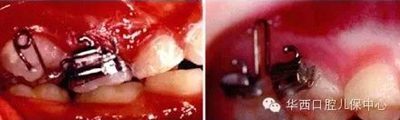

對于間隙已喪失,繼承恒牙無法萌出,則需要通過正畸治療局部開展間隙

使用局部固定矯治器直立后牙

或使用擺式矯治器推磨牙遠(yuǎn)中等